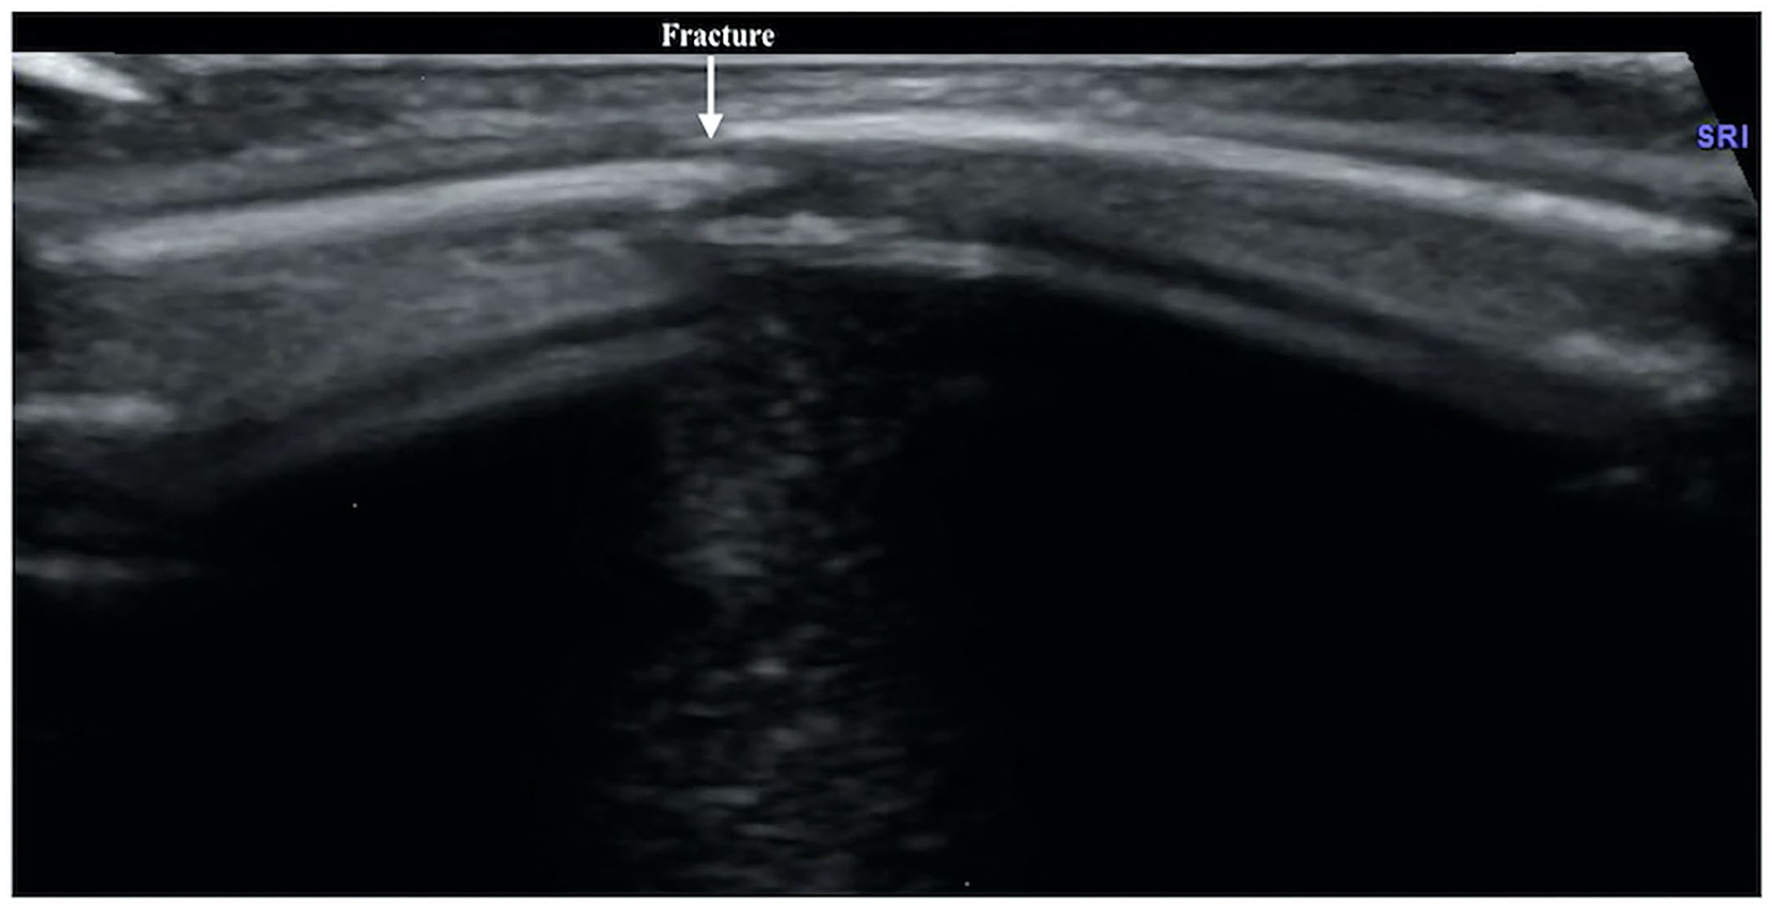

Figure 7

Callus formation. The infant was G1P1, with a gestational age of 39+5 weeks, vaginal delivery, and a birth weight of 3,700 g. The infant was admitted to the hospital on the 7th day after birth due to jaundice. Physical examination revealed local swelling and callus formation on the medial segment of the right clavicle. Ultrasound examination showed interrupted continuity and local bone tissue proliferation forming a callus at this fracture site (within the dashed line).